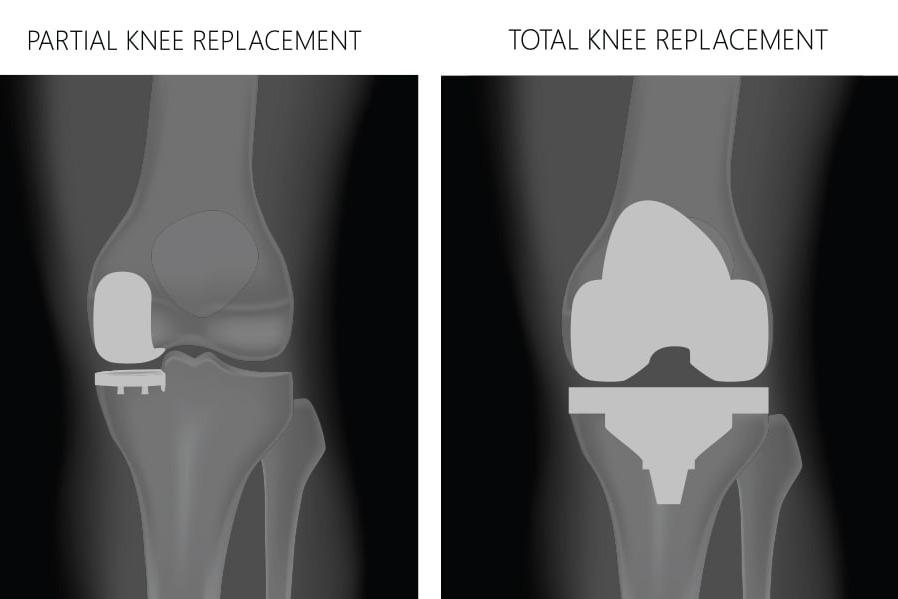

Partial Knee Replacement

Partial Knee Replacement in Jaipur – The Derma Joint Co Knee pain due to arthritis or localized joint damage can limit mobility and reduce quality of life. Partial knee replacement (PKR) is a surgical procedure that replaces only the damaged compartment of the knee while preserving healthy bone and tissue. At The Derma Joint Co, recognized as the best partial knee replacement surgeon in Jaipur, we provide advanced surgical care, precise techniques, and personalized treatment to restore knee function and relieve pain. What is Partial Knee Replacement? Partial knee replacement involves replacing only the affected compartment of the knee (medial, lateral, or patellofemoral) while keeping the healthy parts intact. This procedure is ideal for patients with: Osteoarthritis limited to one part of the knee Localized cartilage damage Knee pain that has not responded to medications or physiotherapy Desire for quicker recovery with minimal surgical intervention Symptoms Indicating the Need for Partial Knee Replacement Persistent knee pain affecting daily activities Stiffness and reduced range of motion Swelling or tenderness in the affected compartment Difficulty walking, climbing stairs, or standing for long periods Chronic pain not relieved by non-surgical treatments Advanced Partial Knee Replacement at The Derma Joint Co At The Derma Joint Co, we provide comprehensive care for partial knee replacement: Accurate Diagnosis – X-rays, MRI, and clinical assessment to identify affected compartments Customized Surgical Planning – tailored prosthesis selection and surgical approach Advanced Surgical Techniques – precise implant placement preserving healthy tissue Post-Surgery Rehabilitation – physiotherapy and exercises for faster recovery and mobility Long-Term Monitoring – regular follow-ups to ensure proper function and prevent complications Why Choose The Derma Joint Co for Partial Knee Replacement in Jaipur? Experienced orthopedic and knee replacement surgeons State-of-the-art surgical facilities and tools Personalized care plans based on patient’s condition Safe, hygienic, and patient-centered clinic environment Trusted as the best partial knee replacement surgeon in Jaipur Tips for Faster Recovery Follow post-surgery physiotherapy and rehabilitation programs Maintain a healthy diet rich in protein and calcium Avoid high-impact activities during early recovery Attend all follow-up appointments for proper monitoring Gradually resume mobility under professional guidance Conclusion Partial knee replacement is an effective solution to relieve pain, restore function, and improve quality of life for patients with localized knee damage. At The Derma Joint Co – the best partial knee replacement surgeon in Jaipur, we provide expert surgical care, personalized rehabilitation, and dedicated follow-up to ensure optimal outcomes. 👉 Book your consultation today at The Derma Joint Co and receive specialized care for partial knee replacement.

Total Knee Replacement

Total Knee Replacement in Jaipur – The Derma Joint Co Knee pain from severe arthritis, injury, or degeneration can significantly affect mobility and quality of life. Total knee replacement (TKR) is a highly effective surgical procedure that replaces damaged knee joint surfaces with advanced prosthetics, restoring function and reducing pain. At The Derma Joint Co, recognized as the best total knee replacement surgeon in Jaipur, we provide expert care, advanced surgical techniques, and personalized treatment plans to help patients regain mobility and independence. What is Total Knee Replacement? Total knee replacement involves removing damaged cartilage and bone from the knee joint and replacing it with a durable prosthetic implant. This procedure is recommended for: Severe osteoarthritis Rheumatoid arthritis Post-traumatic arthritis Deformities or loss of knee function due to injury or disease Symptoms Indicating the Need for Total Knee Replacement Severe, persistent knee pain affecting daily activities Stiffness and limited range of motion Swelling or tenderness in the knee joint Difficulty walking, climbing stairs, or standing for long periods Chronic knee pain not relieved by medications or physiotherapy Advanced Total Knee Replacement at The Derma Joint Co At The Derma Joint Co, we provide comprehensive care for total knee replacement: Accurate Diagnosis – clinical evaluation, X-rays, and MRI scans Customized Surgical Planning – tailored prosthesis selection and surgical approach Advanced Surgical Techniques – precise implant placement for optimal alignment and longevity Post-Surgery Rehabilitation – physiotherapy and exercises to restore mobility and strength Long-Term Monitoring – regular follow-ups to ensure implant function and prevent complications Why Choose The Derma Joint Co for Total Knee Replacement in Jaipur? Experienced orthopedic and knee replacement surgeons State-of-the-art surgical facilities and tools Personalized treatment plans based on patient’s anatomy and condition Safe, hygienic, and patient-focused clinic environment Trusted as the best total knee replacement surgeon in Jaipur Tips for Faster Recovery Follow physiotherapy and post-surgery exercise programs Maintain a balanced diet rich in protein and calcium Avoid high-impact activities during early recovery Attend all follow-up appointments for monitoring and evaluation Gradually resume mobility under professional guidance Conclusion Total knee replacement is a reliable solution to relieve pain, improve mobility, and enhance quality of life. At The Derma Joint Co – the best total knee replacement surgeon in Jaipur, we provide expert surgical care, personalized rehabilitation, and dedicated follow-up to ensure optimal outcomes. 👉 Book your consultation today at The Derma Joint Co and get specialized care for total knee replacement.